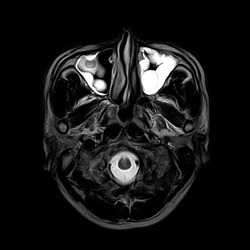

症例は30代の男性。数か月前から続く左目の違和感と頭痛で眼科を受診。眼科精査で異常なく、頭の精査目的に当院紹介となった方です。頭痛は左眉の上に限局しており、下を向くと痛みが増強されました。ここ数か月以内に、風邪に罹患した既往なし。頭部MRI・MRAを撮影し、脳や頭の血管には異常所見は認めませんでしたが、副鼻腔内が白く光って見えており、副鼻腔炎と診断しました。

とくに両側の上顎洞(頬の部分)と左前頭洞(眉の部分)が白く光っており、浸出液や膿がたまっている状態です。